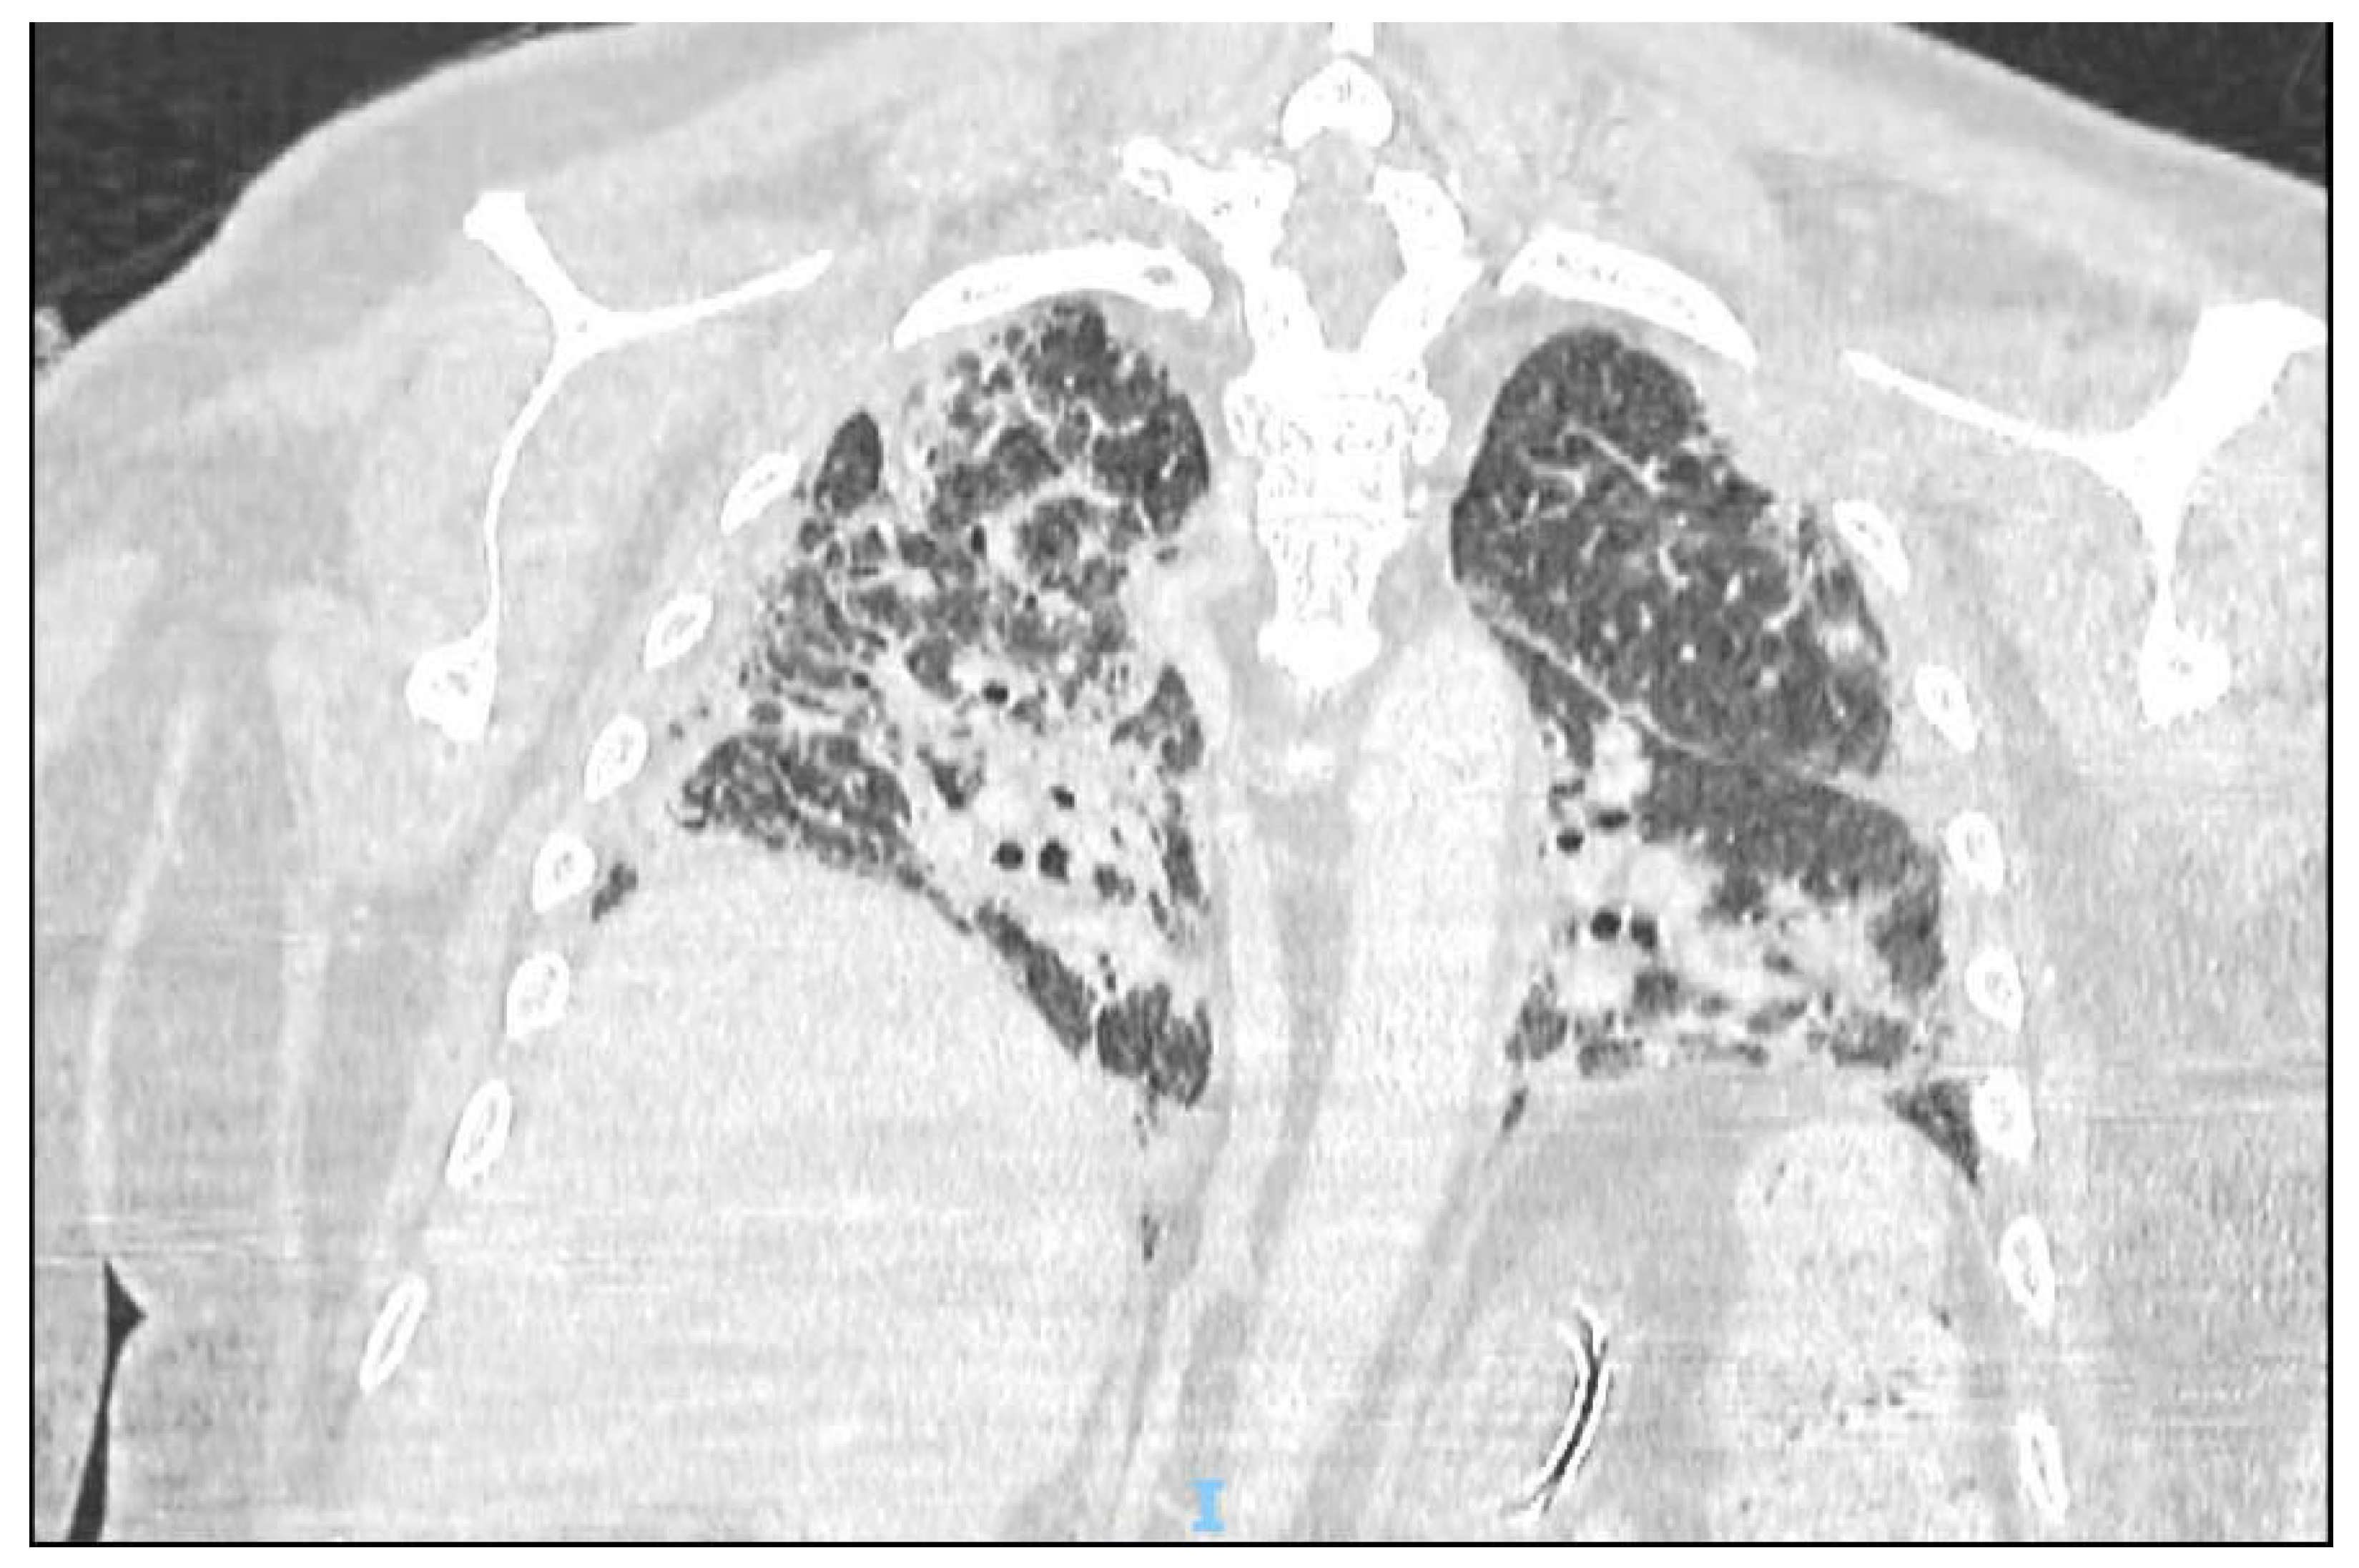

- Garg, M.; Prabhakar, N.; Muthu, V.; Farookh, S.; Kaur, H.; Suri, V.; Agarwal, R. CT Findings of COVID-19-associated Pulmonary Mucormycosis: A Case Series and Literature Review. Radiology 2022, 302, 214–217. [Google Scholar] [CrossRef] [PubMed]